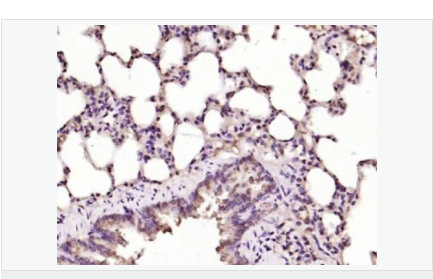

| 英文名稱 | Ferritin Heavy Chain/FTH1 |

| 中文名稱 | 鐵蛋白抗體 |

| 產品應用 | ELISA=1:5000-10000 IHC-P=1:100-500 IHC-F=1:100-500 Flow-Cyt=1ug/Test (石蠟切片需做抗原修復) not yet tested in other applications. optimal dilutions/concentrations should be determined by the end user. |

| 產品介紹 | This gene encodes the heavy subunit of ferritin, the major intracellular iron storage protein in prokaryotes and eukaryotes. It is composed of 24 subunits of the heavy and light ferritin chains. Variation in ferritin subunit composition may affect the rates of iron uptake and release in different tissues. A major function of ferritin is the storage of iron in a soluble and nontoxic state. Defects in ferritin proteins are associated with several neurodegenerative diseases. This gene has multiple pseudogenes. Several alternatively spliced transcript variants have been observed, but their biological validity has not been determined. [provided by RefSeq, Jul 2008]. Function: Stores iron in a soluble, non-toxic, readily available form. Important for iron homeostasis. Has ferroxidase activity. Iron is taken up in the ferrous form and deposited as ferric hydroxides after oxidation. Also plays a role in delivery of iron to cells. Mediates iron uptake in capsule cells of the developing kidney. Subunit: Oligomer of 24 subunits. There are two types of subunits: L (light) chain and H (heavy) chain. The major chain can be light or heavy, depending on the species and tissue type. The functional molecule forms a roughly spherical shell with a diameter of 12 nm and contains a central cavity into which the insoluble mineral iron core is deposited. Subcellular Location: Cytoplasmic. Tissue Specificity: In human liver the heavy chain is the major chain. Similarity: Belongs to the ferritin family. Contains 1 ferritin-like diiron domain. SWISS: P02794 Gene ID: 2495 Database links: Entrez Gene: 2495 Human Entrez Gene: 14319 Mouse Entrez Gene: 100173063 Orangutan Omim: 134770 Human SwissProt: P02794 Human SwissProt: P09528 Mouse SwissProt: Q5R8J7 Orangutan Unigene: 524910 Human Unigene: 645560 Human Unigene: 1776 Mouse Important Note: This product as supplied is intended for research use only, not for use in human, therapeutic or diagnostic applications. |